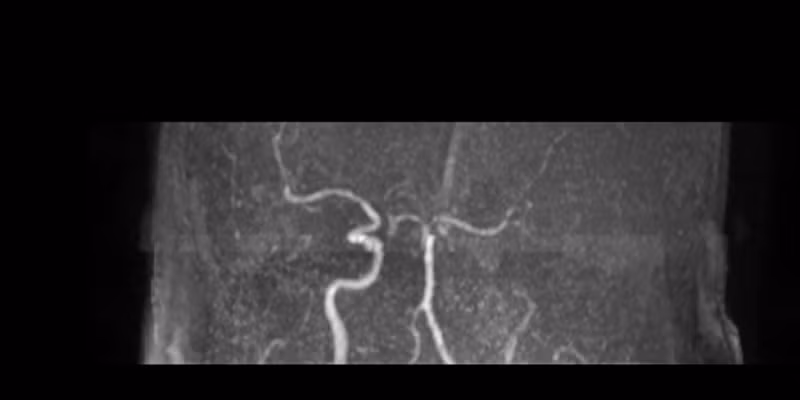

Ngay lập tức, bệnh nhân được chụp MRI sọ não, kết quả cho thấy tắc động mạch cảnh trong – não trước – não giữa bên trái, đặc biệt tắc động mạch não trước đoạn A2 phải, gây nhồi máu não ổ bán cầu trái.

phim-mri-truoc-can-thiep.png

Phim MRI trước can thiệp.